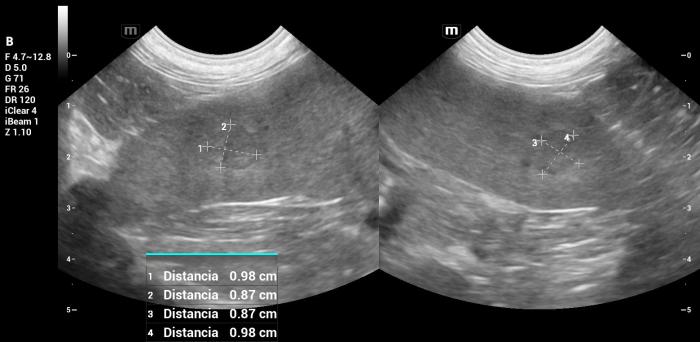

2. Lesión menor (cola) (Figura 20):

- Ligeramente hipoecoica, de 0.98 × 0.98 × 0.87 cm.

- Doppler positivo.

- Sin zonas sugerentes de cavitación o mineralización.